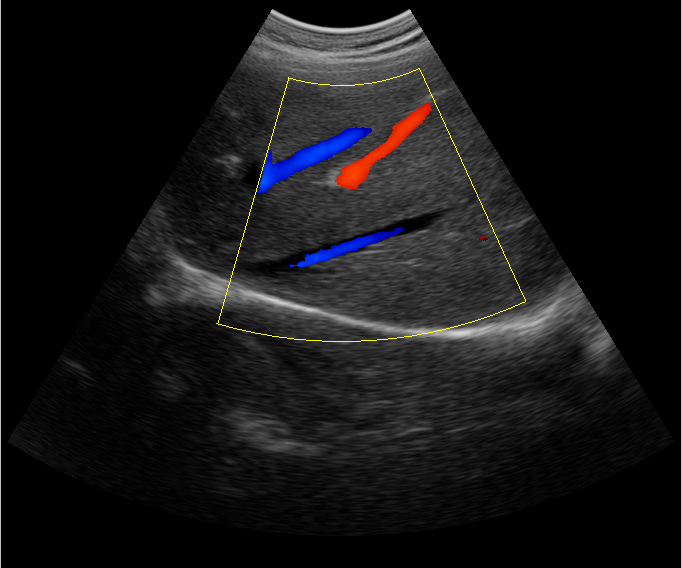

B超檢查主要是檢測(cè)肝臟的外形、大小、膽囊、門(mén)靜脈、回聲粗線(xiàn)等問(wèn)題。由于乙肝病毒造成肝細(xì)胞破損嚴(yán)重,肝細(xì)胞出現(xiàn)問(wèn)題,發(fā)生異常外形就會(huì)改變,通過(guò)B超檢查就能很清楚的檢查出肝臟受損的程度,以及肝臟的大小是否改變,肝臟是否發(fā)展為肝纖維化、肝硬化等。還可以檢查門(mén)靜脈主干內(nèi)徑是否增寬等情況。

肝臟B超還可以通過(guò)肝臟的門(mén)靜脈、回聲粗線(xiàn)、膽囊等指標(biāo)來(lái)診斷病情。由于肝炎病毒長(zhǎng)期侵害會(huì)造成肝細(xì)胞破損嚴(yán)重,肝細(xì)胞出現(xiàn)異常,肝臟發(fā)生異常時(shí)外形就會(huì)改變。通過(guò)肝臟B超檢查就能很清楚地看出肝臟的受損程度,以及肝臟的大小、形態(tài)、回聲等是否正常。有利于肝臟的疾病的正確診斷。